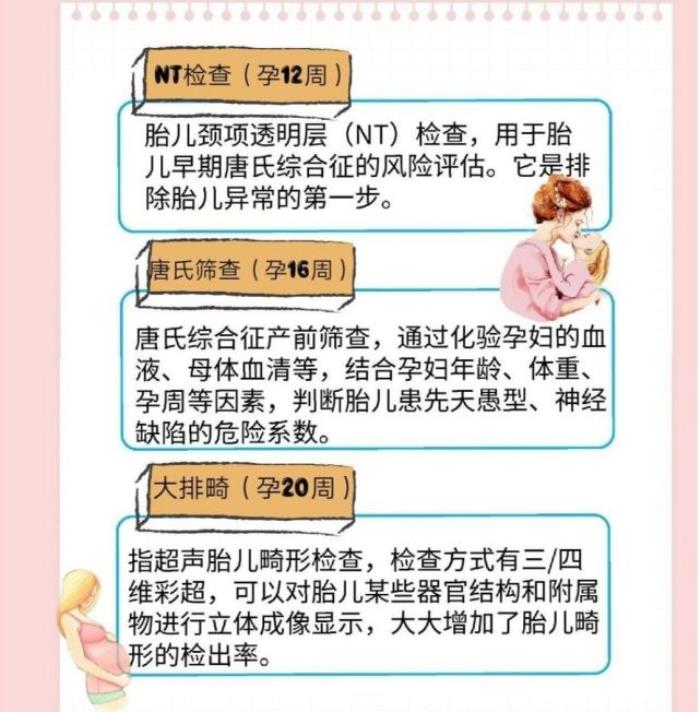

查一、NT检查

检查时间:怀孕11-14周

这项检查主要通过 检查胎儿的 “颈部透明带” 的厚度,判断胎儿存在唐氏综合症的概率;属于 孕期第一次“排畸筛查”,而且是关于胎儿智力缺陷方面的筛查。

这次检查对时间要求很严格,因为 颈部透明带 只有在这段时间存在,过了14周后就逐渐消失看不到了。

如果检查结果,发现胎儿的 NT值超过3mm,就说明胎儿存在唐氏综合症的概率较高,要听从医生的建议,进一步排查;但孕妈也不要太焦急,这毕竟只是筛查,只能说明宝宝存在的几率较高,并不是完全确诊。

检查二、唐氏筛查

检查时间:怀孕16周左右

这是孕期的 第二次“排畸筛查”,也主要 筛查胎儿智力缺陷,根据检查结果再结合孕妈的怀孕周数、年龄、体重等数据,来综合 判断胎儿患“唐氏综合症”的危险系数有多高。

如果检查结果显示:唐氏临界值或高危,只能说明胎儿患这个病的几率较高,但并不是确诊,这项检查的准确率只有60%-70%,需要做进一步排查,因而孕妈不要太焦虑。